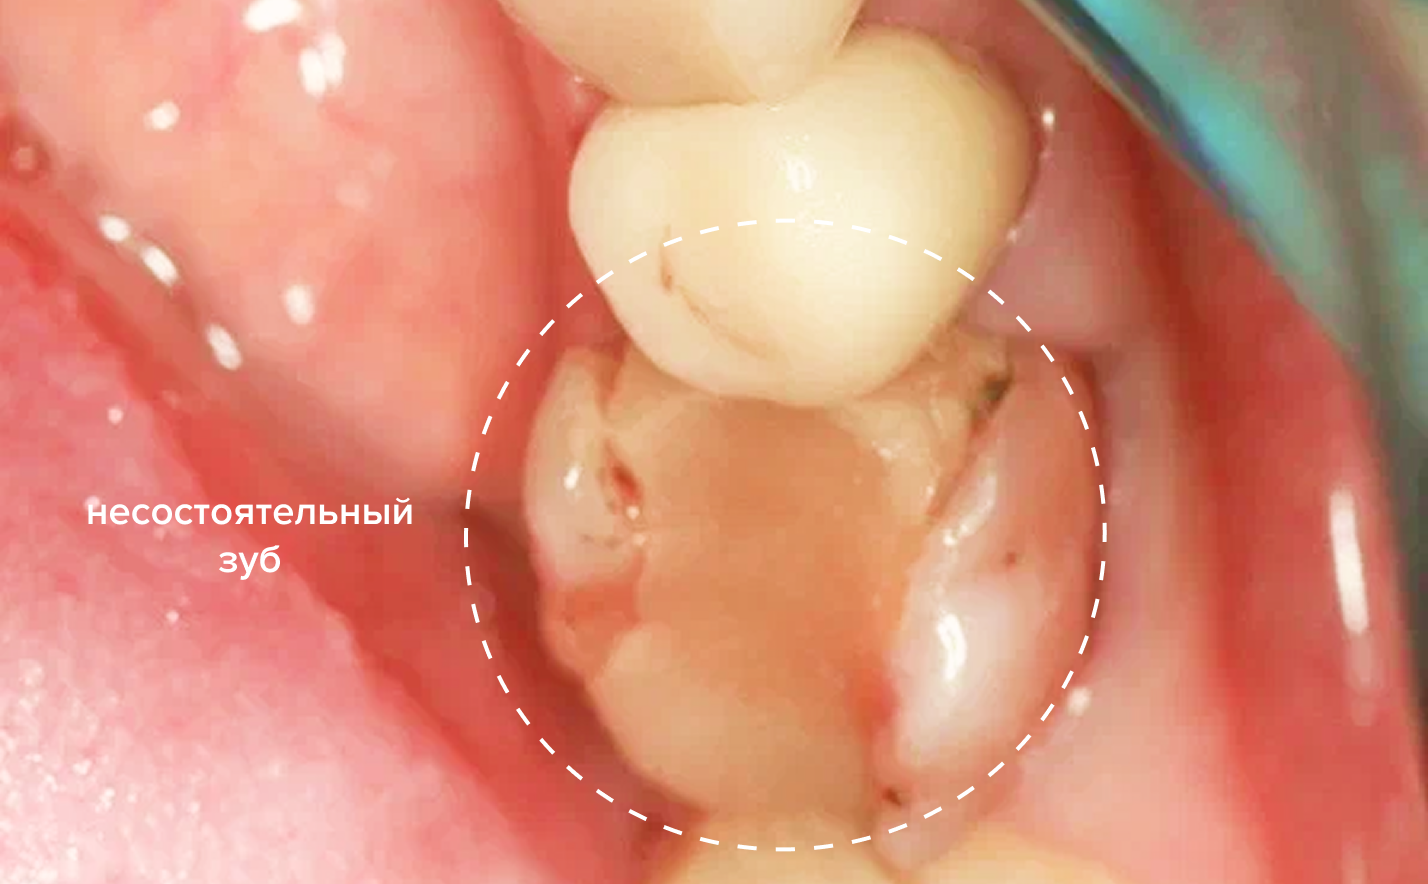

До и после

До

После